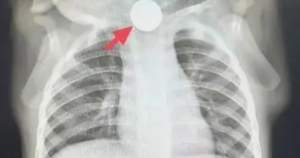

Đau vai không rõ nguyên nhân có phải là dấu hiệu của ung thư gan?

Các báo cáo ca bệnh đã ghi nhận đau vai có thể là triệu chứng